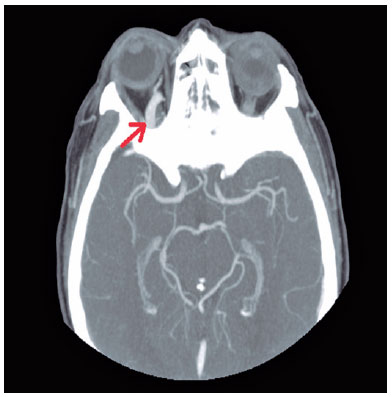

After these findings, cranial and orbital contrast computed tomography was performed. Computed tomography showed a marked increase in the caliber of the right superior ophthalmic vein, compatible with an arteriovenous fistula (Figure 1). A consultation was made with the Radiology Department, which indicated a preferential evaluation for a possible transarterial embolization. One week later, the appointment was postponed indefinitely because of the declaration of state of alarm due to Covid-9.